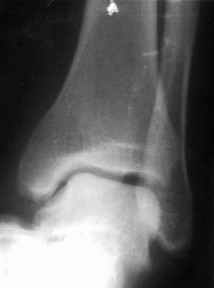

братился мужчина, 50 лет. Жалобы на боли в голеностопном суставе, периодическое подворачивание стопы вовнутрь. Получил травму 5 лет назад. При осмотре - признаки латеральной нестабильности, боли по ходу малоберцово-таранной, задней малоберцово-пяточной связки. Сделал стандартный Rg, и Rg с нагрузкой. В течение последнего года начали беспокоить боли в коленном, тазобедренном суставе. Как полагаю, это связано с нарушением биомеханики всей ноги. Если прооперировать и устранть нестабильность, пройдут ли эти боли (этот вопрос пациент задал сразу, как только услышал слово операция)? С ув. Сергей Мелашенко, Приморск, Запорожская обл. Ukraine

Попробуйте сделать аналогичный стресс -снимок прямой проекции здорового сустава и сравнив его с ранее травмированной стороной определитесь есть

нестабильность или нет.

присоединяюсь к мнению показать симметричные снимки

пока не кажется, что нестабильность очевидна.